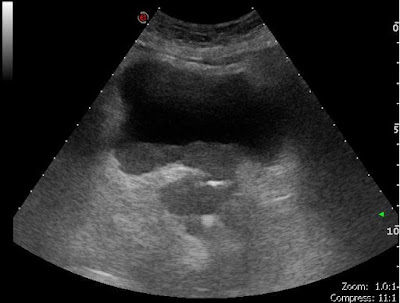

„D”: pseudodiverticulumA BPH által fenntartott krónikus pangás állandó magasabb nyomást eredményez a húgyhólyagban.Következményesen létrejött hypertrophisált izomzatú hólyag látszik pseudodiverticulomokkal (csak a kiboltosuló nyálkahártya alkotja a...